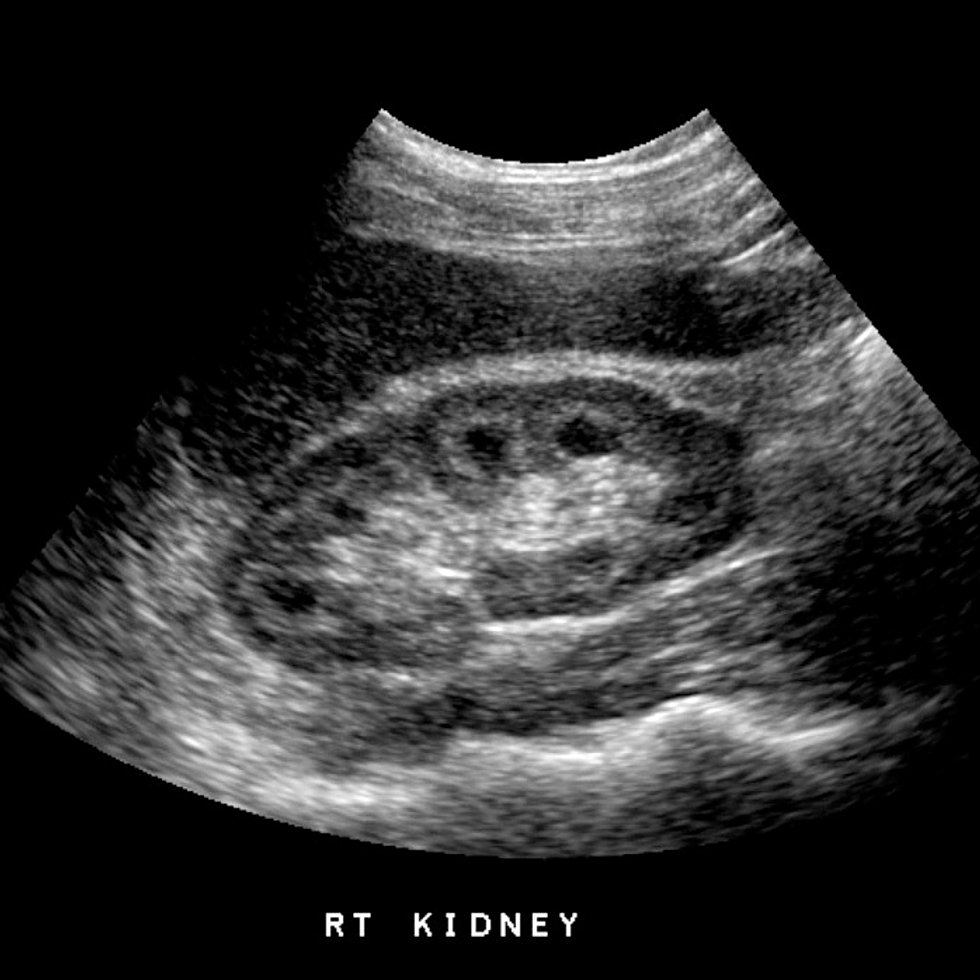

Dialysis machines amazon. Manufacturers carolina organic supply company, ipu, spectrum. Dialysis in jamaica montego bay. Kidney [kid´ne] either of the two beanshaped organs in the lumbar region that filter the blood, excreting the endproducts of frame metabolism inside the form of urine. Kidney failure treatment in bangalore kidney disease. Kidney failure treatment in bangalore nu hospitals providing quality treatment for chronic kidney disease and failure in bangalore, india. Kidney dialysis get expert advice yearend.Cut price. Cause of kidney dialysis. Seek our easytoread related content. Heaps of subjects discover solutions at reference now! Kidney dialysis get professional recommendation yearend.Bargain. Zierlich international dialysis centre. Zierlich is a country of the art dialysis centre located in a contemporary purposebuilt clinical centre (gwest) in montego bay, jamaica.